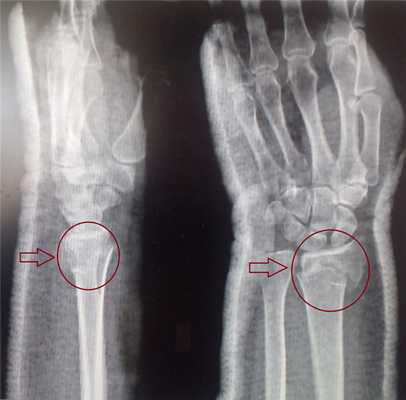

Рентгенологически (в двух проекциях) уточняют место и особенности перелома. При эпифизеолизе у детей в сомнительных случаях делают сравнительную рентгенографию здоровой руки.

Перелом дистального метаэпифиза лучевой кости (перелом лучевой кости «в типичном месте»)

Перелом дистального метаэпифиза лучевой кости («луч в типичном месте»)

Дистальный метаэпифиз - это нижний конец лучевой кости, расположенный рядом с кистью.

Перелом «луча в типичном месте» обычно возникает при прямом падении на вытянутую руку. Помимо резкой боли в руке, может появиться штыкообразная деформация, изменение положения кисти. В процесс перелома бывают вовлечены нервы и сосуды запястья, которые могут быть поджаты отломками, что проявляется онемением в пальцах, похолоданием кисти.

Для уточнения характера перелома и выбора дальнейшей тактики лечения используется рентгенография, в ряде случаев - компьютерная томография. Иногда требуется УЗИ кистевого сустава.